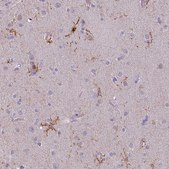

Monoclonal Anti-ITGAM Prestige Antibodies® Powered by Atlas Antibodies is developed and validated by the Human Protein Atlas (HPA) project . Each antibody is tested by immunohistochemistry against hundreds of normal and disease tissues. These images can be viewed on the Human Protein Atlas (HPA) site by clicking on the Image Gallery link. The antibodies are also tested using protein array and western blotting. To view these protocols and other useful information about Prestige Antibodies and the HPA, visit sigma.com/ Prestige.

- IHC tissue array of 44 normal human tissues and 20 of the most common cancer type tissues.